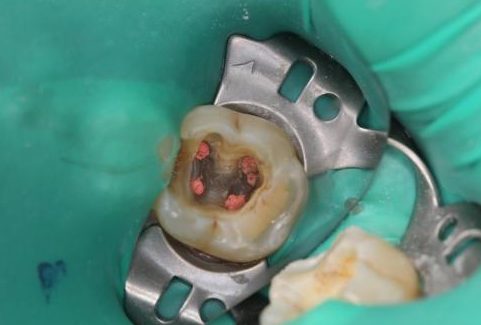

有啲牙齒嘅根管出現感染問題,其實好多人都唔知根管感染會點樣?

維港口腔醫生為大家科普,根管感染有明顯嘅症狀,例如進食或飲水時感到疼痛,尤其係食過熱或過冷嘅食物;咀嚼時牙齒出現疼痛。

之後隨著感染嘅進展,呢啲症狀通常會喺牙髓壞死後消失。不過大家唔好因此認為牙痛已經好咗,實際上感染可能已經通過根管系統擴散,影響周圍嘅軟組織,甚至可能波及到牙槽骨。最終未經妥善處理嘅根管感染可能表現為以下幾點症狀:

感染擴散範圍越大,杜牙根治療嘅機會就會減小,最終可能需要剝牙,仲可能導致嚴重嘅頜面部感染。因此維港口腔醫生建議對於有根管感染嘅情況要及早治療,以避免症狀嘅加重和並發症嘅發生。